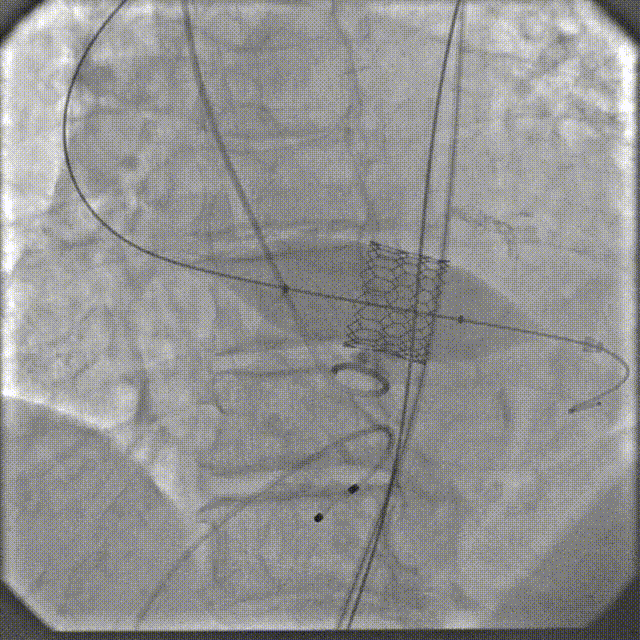

手术过程

瓣膜系统过弓

定位造影

瓣膜确认位置后释放

回收极限处造影

最终造影

术后复查造影示瓣膜位置满意,形态良好,冠脉显影良好;TTE示轻微瓣周漏;排除入路血管问题,手术圆满成功。

第三例为主动脉瓣反流挑战性病例,超声心动图提示主动脉瓣退行性变伴重度反流,解剖特征包括:瓣环周长78mm(平均直径24.8mm)呈椭圆形态(D/S比值1.25),窦部扩张(STJ直径34mm)但瓣叶无增厚及钙化(钙化积分0),同时合并左室显著扩大(LVEDD 72mm)伴室壁变薄(室间隔厚度4.5mm)。该纯反流病例面临双重技术挑战:无钙化瓣环及瓣吐:主动脉根部与心室轴成角60°横位心。蔡新勇教授,谢国波教授,詹宇亮博士,朱虹岷博士,刘松涛医生手术团队应用无冠窦支点法,将瓣环作为主要锚定区,并采用可调弯输送系统提高同轴性,术中根据瓣架位置及受力情况,结合TTE超声实时监测瓣膜位置,最终实现瓣膜精准释放。